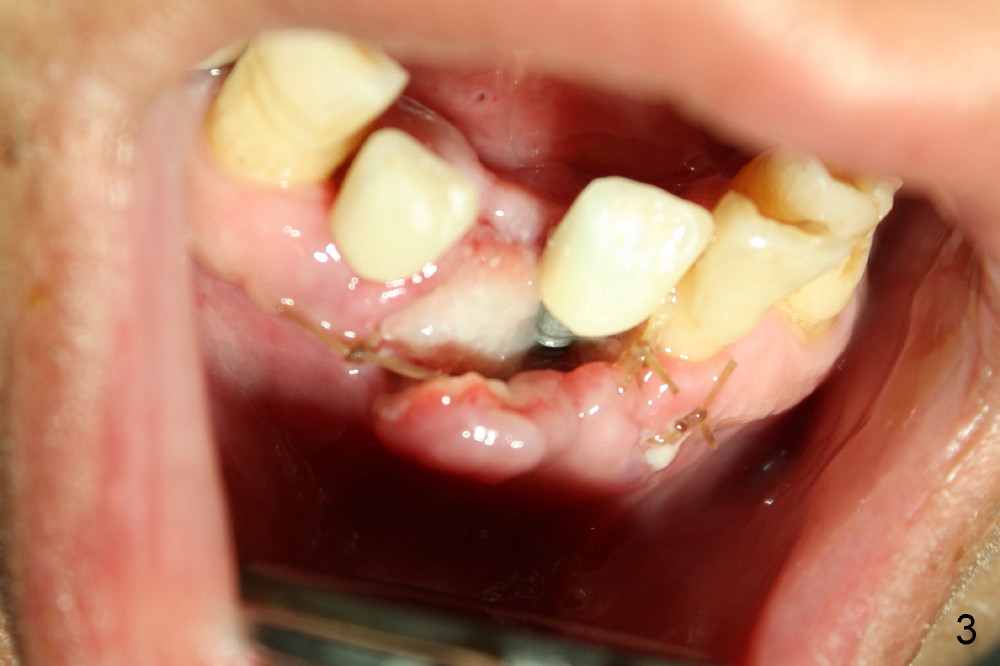

The mesial incision is found to dehiscence 7 days postop (Fig.3). Perio dressing dislodges one day postop. Perio dress is re-applied at follow up, but it is detached soon. Fortunately the wound shows sign of healing 14 days postop (Fig.4). The wound heals 5 weeks postop, although the top microthreads are exposed (Fig.5). In all, incision should be avoided as much as for immediate implants, anterior and posterior.

The patient plans to travel abroad. Two months ten days postop, the provisionals are removed for preparation for definitive FPD; the gingiva re-attaches to the implant at the site of #24 (Fig.6). The wound dehiscence is thought to be due to over placement of bone graft.